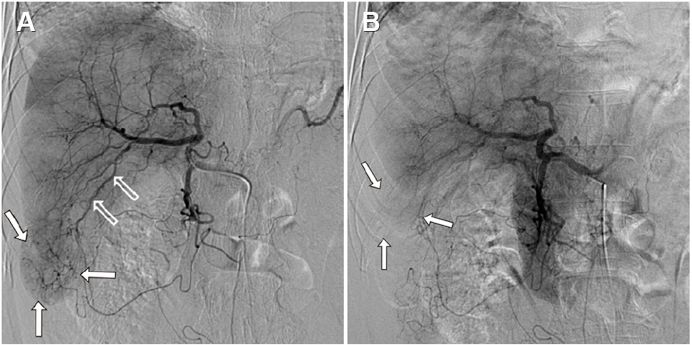

A Ruptured Metastatic Hepatic Gastrointestinal Stromal Tumor Treated by Angiographic Embolization.

Jang SJ, Kwon JH, Han Y.

Department of Radiology, Dongguk University Ilsan Hospital, Goyang, Korea.

Korean J Gastroenterol. 2018 Oct 25;72(4):205-208.

IF:NA

患者70岁男性,3年前接受胃肿瘤的手术切除术,病理提示胃间质瘤,核分裂像29/50HPF,术后肝转移,接受伊马替尼治疗2.5年。本次因右下腹痛伴右肩放射痛急诊入院,血压136/59mmHg,脉搏75bpm,体温正常,右下腹压痛反跳痛+,血常规提示HB11g/dl,腹部CT提示膈下与肝被膜下血肿,肝左右叶可见多发低密度结节,可见肿瘤破裂;急诊血管造影下进行出血血管分支的栓塞后,患者疼痛症状缓解,生命体征稳定。患者出院后继续伊马替尼治疗。

简价

GIST破裂出血是一件非常凶险的事情,肿瘤破裂在腹腔可能会引起致命性的大出血,肝脏转移局部破裂可能因肝被膜的存在而使得出血减缓,但会带来明显的肝区疼痛。对于腹膜转移破裂出血,更多的情况下急诊开腹手术是第一选择,对于相对局限的肝转移部分破裂出血,肝动脉栓塞是另一种有效的急诊手段。笔者所经历的的几例GIST破裂出血,全部都选择了开腹手术,一方面与当时的病情相关,另一方面也有切除耐药病灶的考虑有关;对于破裂出血的病灶,多数均为现有治疗TKI无效或耐药,因此,本病例中,栓塞后继续选择伊马替尼,笔者觉得可能不是最佳选择,话说回来,在合并破裂有再次出血风险的情况下,换用舒尼替尼等抗血管生成药物同样也存在增加出血的风险。不好选择,不知列位如何看待这个问题?